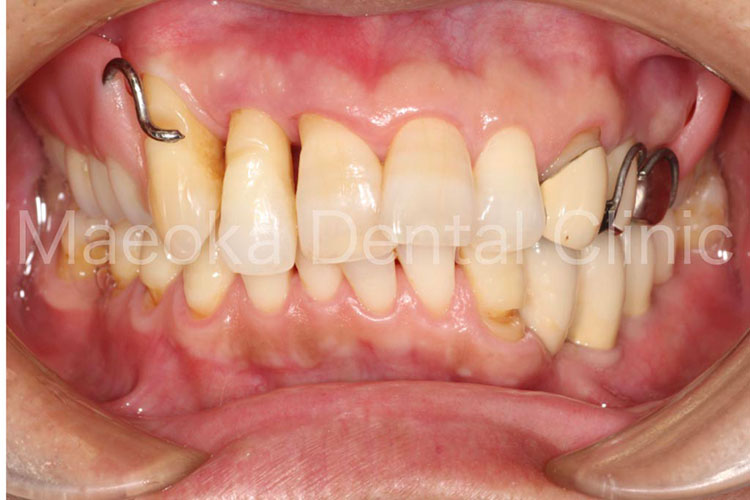

患者さんは54歳の女性の方で、「歯茎がすごく腫れているんですが、こんな口の中でも良くなりますか?」という主訴で来院されました。

初診の際には歯肉の腫脹と発赤が強く、右上には大きなサイナストラクト(歯肉にできた膿の出口)がありました。お話を伺うとご両親の介護で疲れ、なかなか自分の口の中までケアができていないということでした。

具体的な治療内容は治療を進める中で決めていくこととなり、先ずは現在のお口の中で一番の問題になっている歯周病の根本的な原因を取り除いていくところから治療をスタートしています。

患者さんの努力によって歯肉の状態が劇的に改善してきたタイミングで、不適切な被せ物をやり直すこととなりました。歯肉よりも上に健全な歯が残っていない箇所はExtrusion処置(歯を引っ張り出す処置)などを併用した上で、メタルセラミックスとゴールドクラウン、コンポジットレジンにて修復治療を終えています。

全体的な歯列不正(歯並びの乱れ)については、特に問題を生じていなかったため、現在のところ介入は不要と判断しています。

治療を通して患者さん自身のお口に対する意識が変わり、食生活も大きく改善されたことで長期的な安定が見込めるお口の環境になりました。

治療前(正面)

治療後(正面)